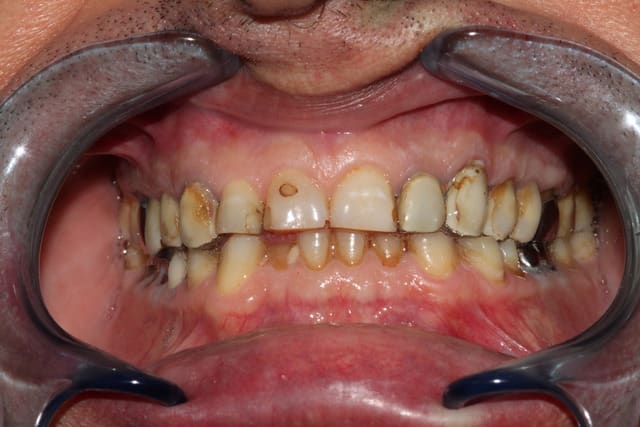

Moi, je suis content de ce type de traitement qui se maintienne dans le temps.

25 ans, ni le paro ni moi le pensions en 88.

Les 2 composites ont été changes 3 ou 4 fois.